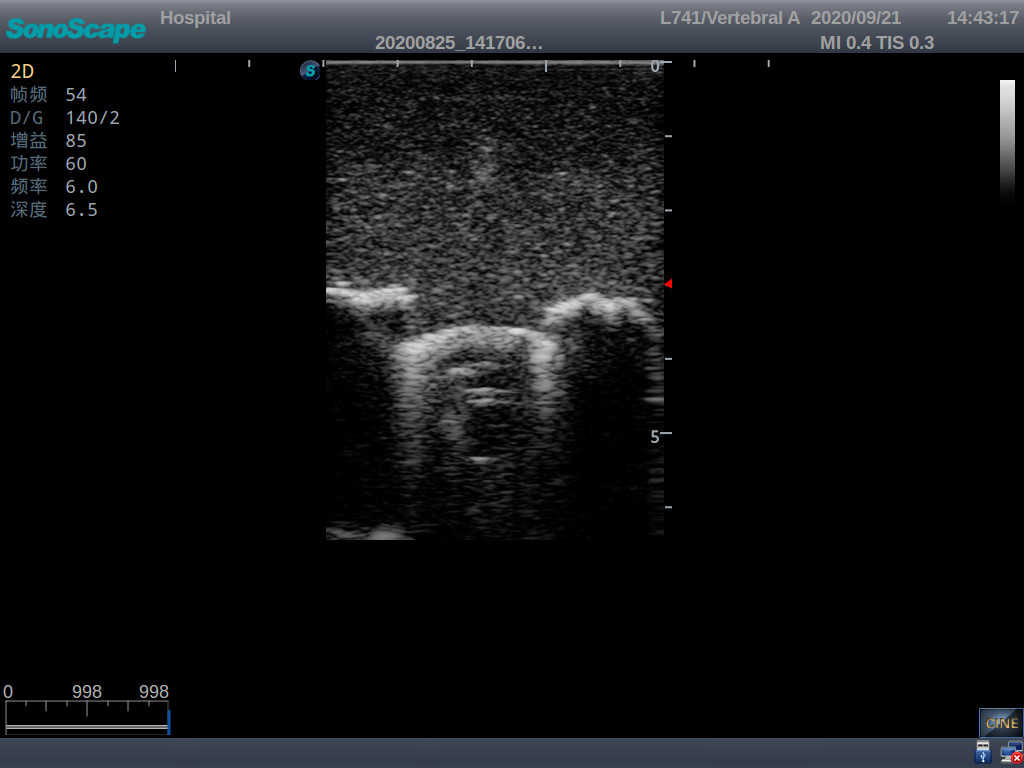

Pediatric Lumbar Puncture Ultrasound Training Model

This model is an ideal choice for ultrasound-guided pediatric lumbar puncture training with true-to-life skin feel and touch, accurate anatomical structures as well as real clinical ultrasound images. Realistic resistance to needle tips and correct landmarks provide excellent hands-on experience.

Accurate anatomical structure of L1-L5 and the vertebral canal

2)  Real clinical ultrasound images

3)  Compatible with various real ultrasound machines

1)  Ultrasound-guided lumbar puncture practice